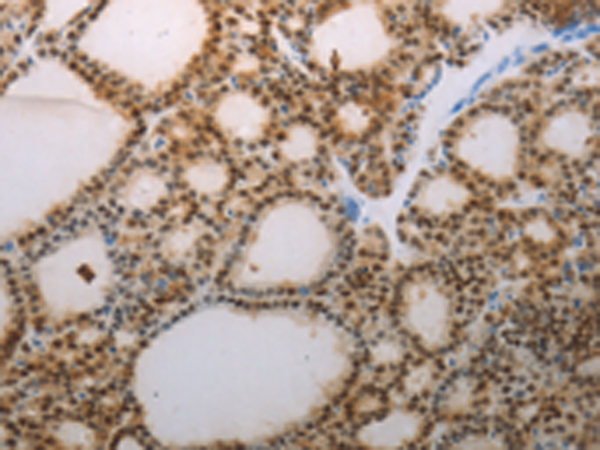

分类: 科研抗体货号: P11104别名: YC1, MSSP, SCR2, HCC-4, MSSP-1, MSSP-2, MSSP-3, C2orf12应用: IHC反应种属: Human, Mouse, Rat